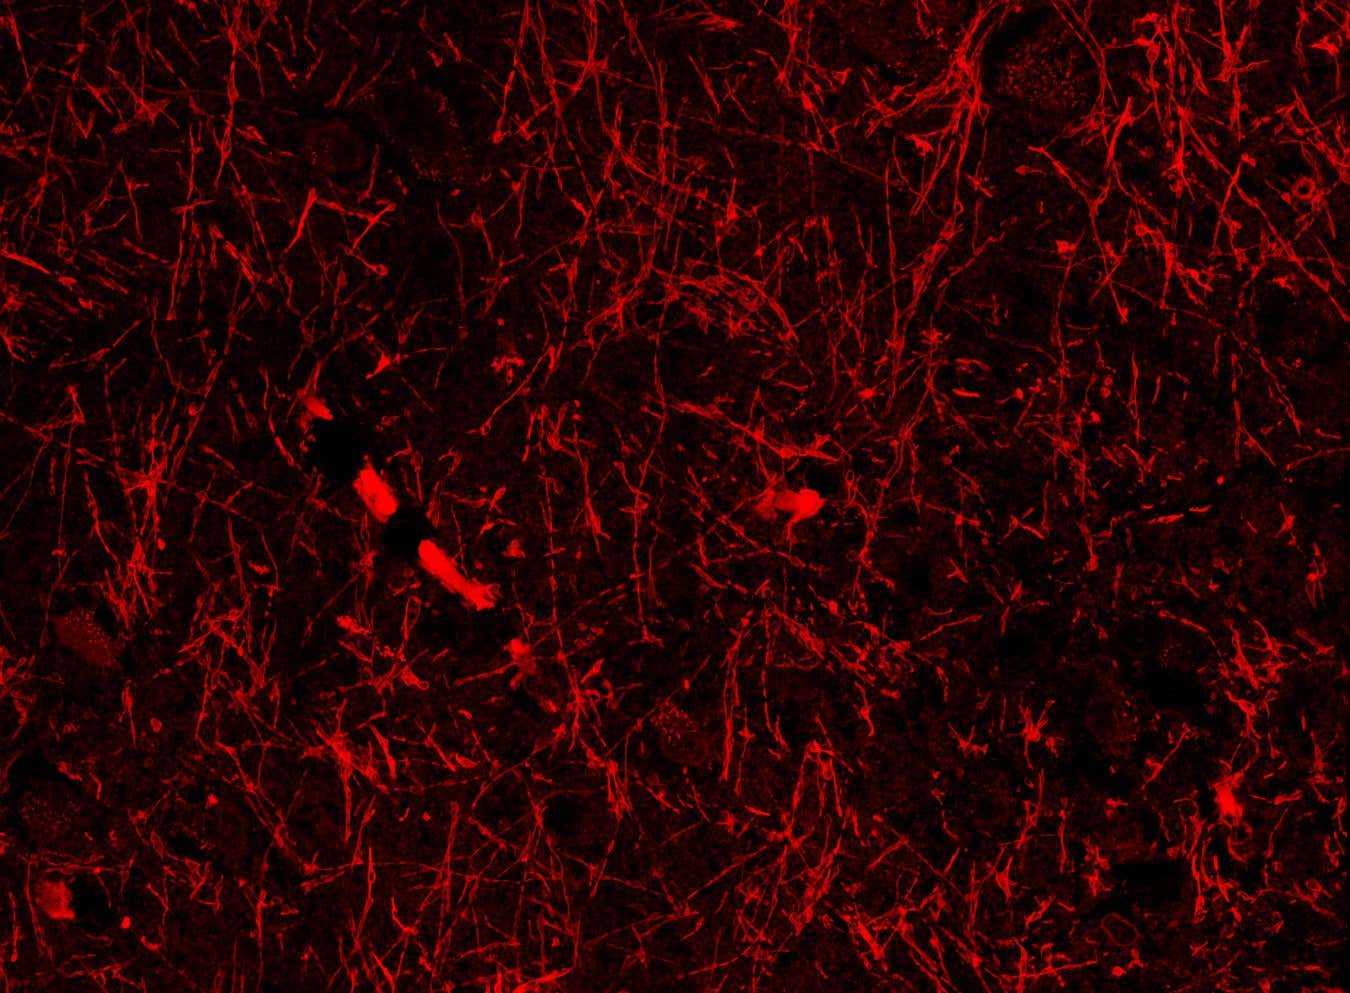

BACKGROUND: Lmods (leiomodins) are critical for the assembly and maintenance of thin filaments in striated muscles by allowing thin filament elongation at the pointed ends. Lmod2’s elongation function has been linked to both actin-binding sites (ABSs) 2 and 3, while the existence and function of an N-terminal ABS1 has been debated. METHODS: To elucidate the little-known role of Lmod2’s ABS1, we created a mutant (F64D/L69D/W72D/W73D: Lmod2-quadruple mutant) predicted to decrease the binding of ABS1 to actin. We analyzed the effect of the mutations using several in vitro, cellular, and in vivo assays. RESULTS: By disrupting the interaction of Lmod2 ABS1 with actin in isolated cardiomyocytes and in mice, we engineered a super Lmod2 that results in remarkably longer thin filaments.